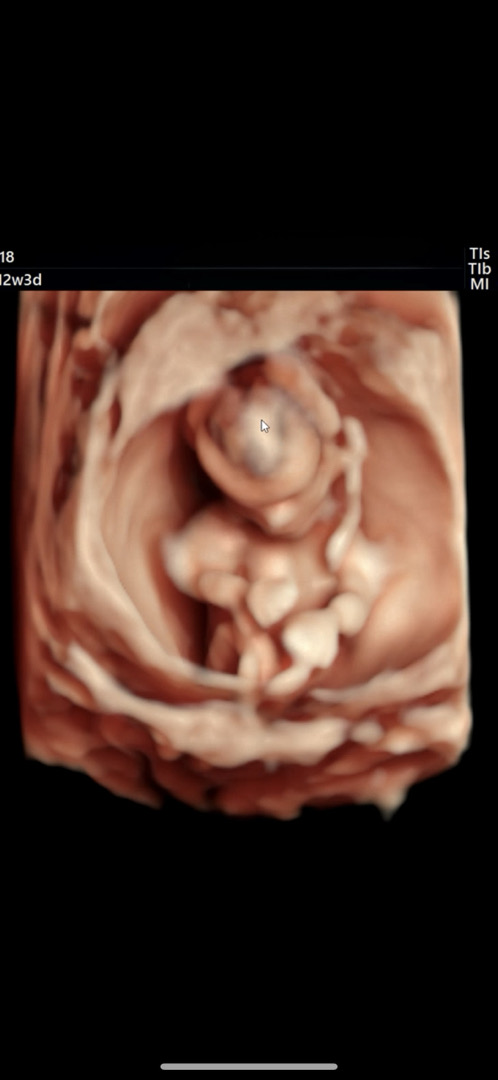

아들맘 확정ღ

니프티결과 나왔는데 다행히 저위험군이고 남아라고 문자 왔는데 너무 좋아서 표정을 못 숨겼네용..ㅎㅎㅎ입체초음파 보고 아들같긴 했는데 아들이라 너무너무 좋아요💕 ʚ♥ɞ